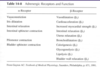

what receptors do epi/NE bind?

- Epi and NE can either bind to either alpha-receptors or beta-receptors. There are several subtypes of each receptor.

- The important thing I want you to remember: The effect will depend on which receptor gets bound.

- Don’t memorize all this. Just realize the theme of hormone activity.

- Think of epinephrine as a hormone, whose activity depends on which receptor it binds.

- You can have totally opposite effects depending on the receptor.